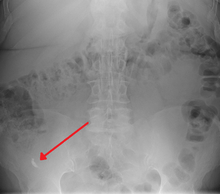

Appendicolith as seen on plain X-ray

In general, plain abdominal radiography (PAR) is not useful in making the diagnosis of appendicitis and should not be routinely obtained from a person being evaluated for appendicitis.[52][53] Plain abdominal films may be useful for the detection of ureteral calculi, small bowel obstruction, or perforated ulcer, but these conditions are rarely confused with appendicitis.[54] An opaque fecalith can be identified in the right lower quadrant in fewer than 5% of people being evaluated for appendicitis.[39] A barium enema has proven to be a poor diagnostic tool for appendicitis. While failure of the appendix to fill during a barium enema has been associated with appendicitis, up to 20% of normal appendices do not fill.[54]